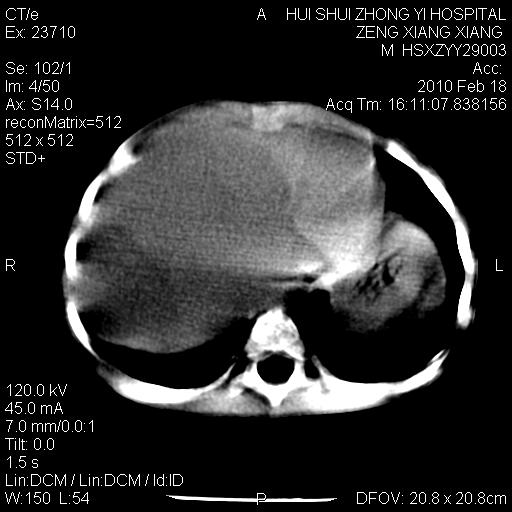

标题: PED3106:男,2岁,腹胀1月。 [打印本页]

标题: PED3106:男,2岁,腹胀1月。

定位腹膜后,肾上腺来源;

定性:恶性神经源性,肾上腺神经节母细胞瘤可能性大。

鉴别:肝母、肾母、肝脏中胚层错构瘤。

依据:年龄、有钙化,肾脏及肝脏受压移位。

肝母细胞瘤可能性大,右肾形态大体可见,不支持肾母细胞瘤,右肾移位不明显,肾上腺神经母细胞瘤可能性不大。